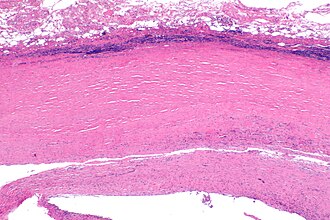

Micrograph of a pleural plaque. H&E stain. (WC/Nephron) | |

| LM | hyaline (fibrosis) material +/-calcifications |

| LM DDx | fibrosing pleuritis, malignant mesothelioma - especially desmoplastic mesothelioma |

Microscopic

Features:[3]

- Hyaline material +/- calcification.